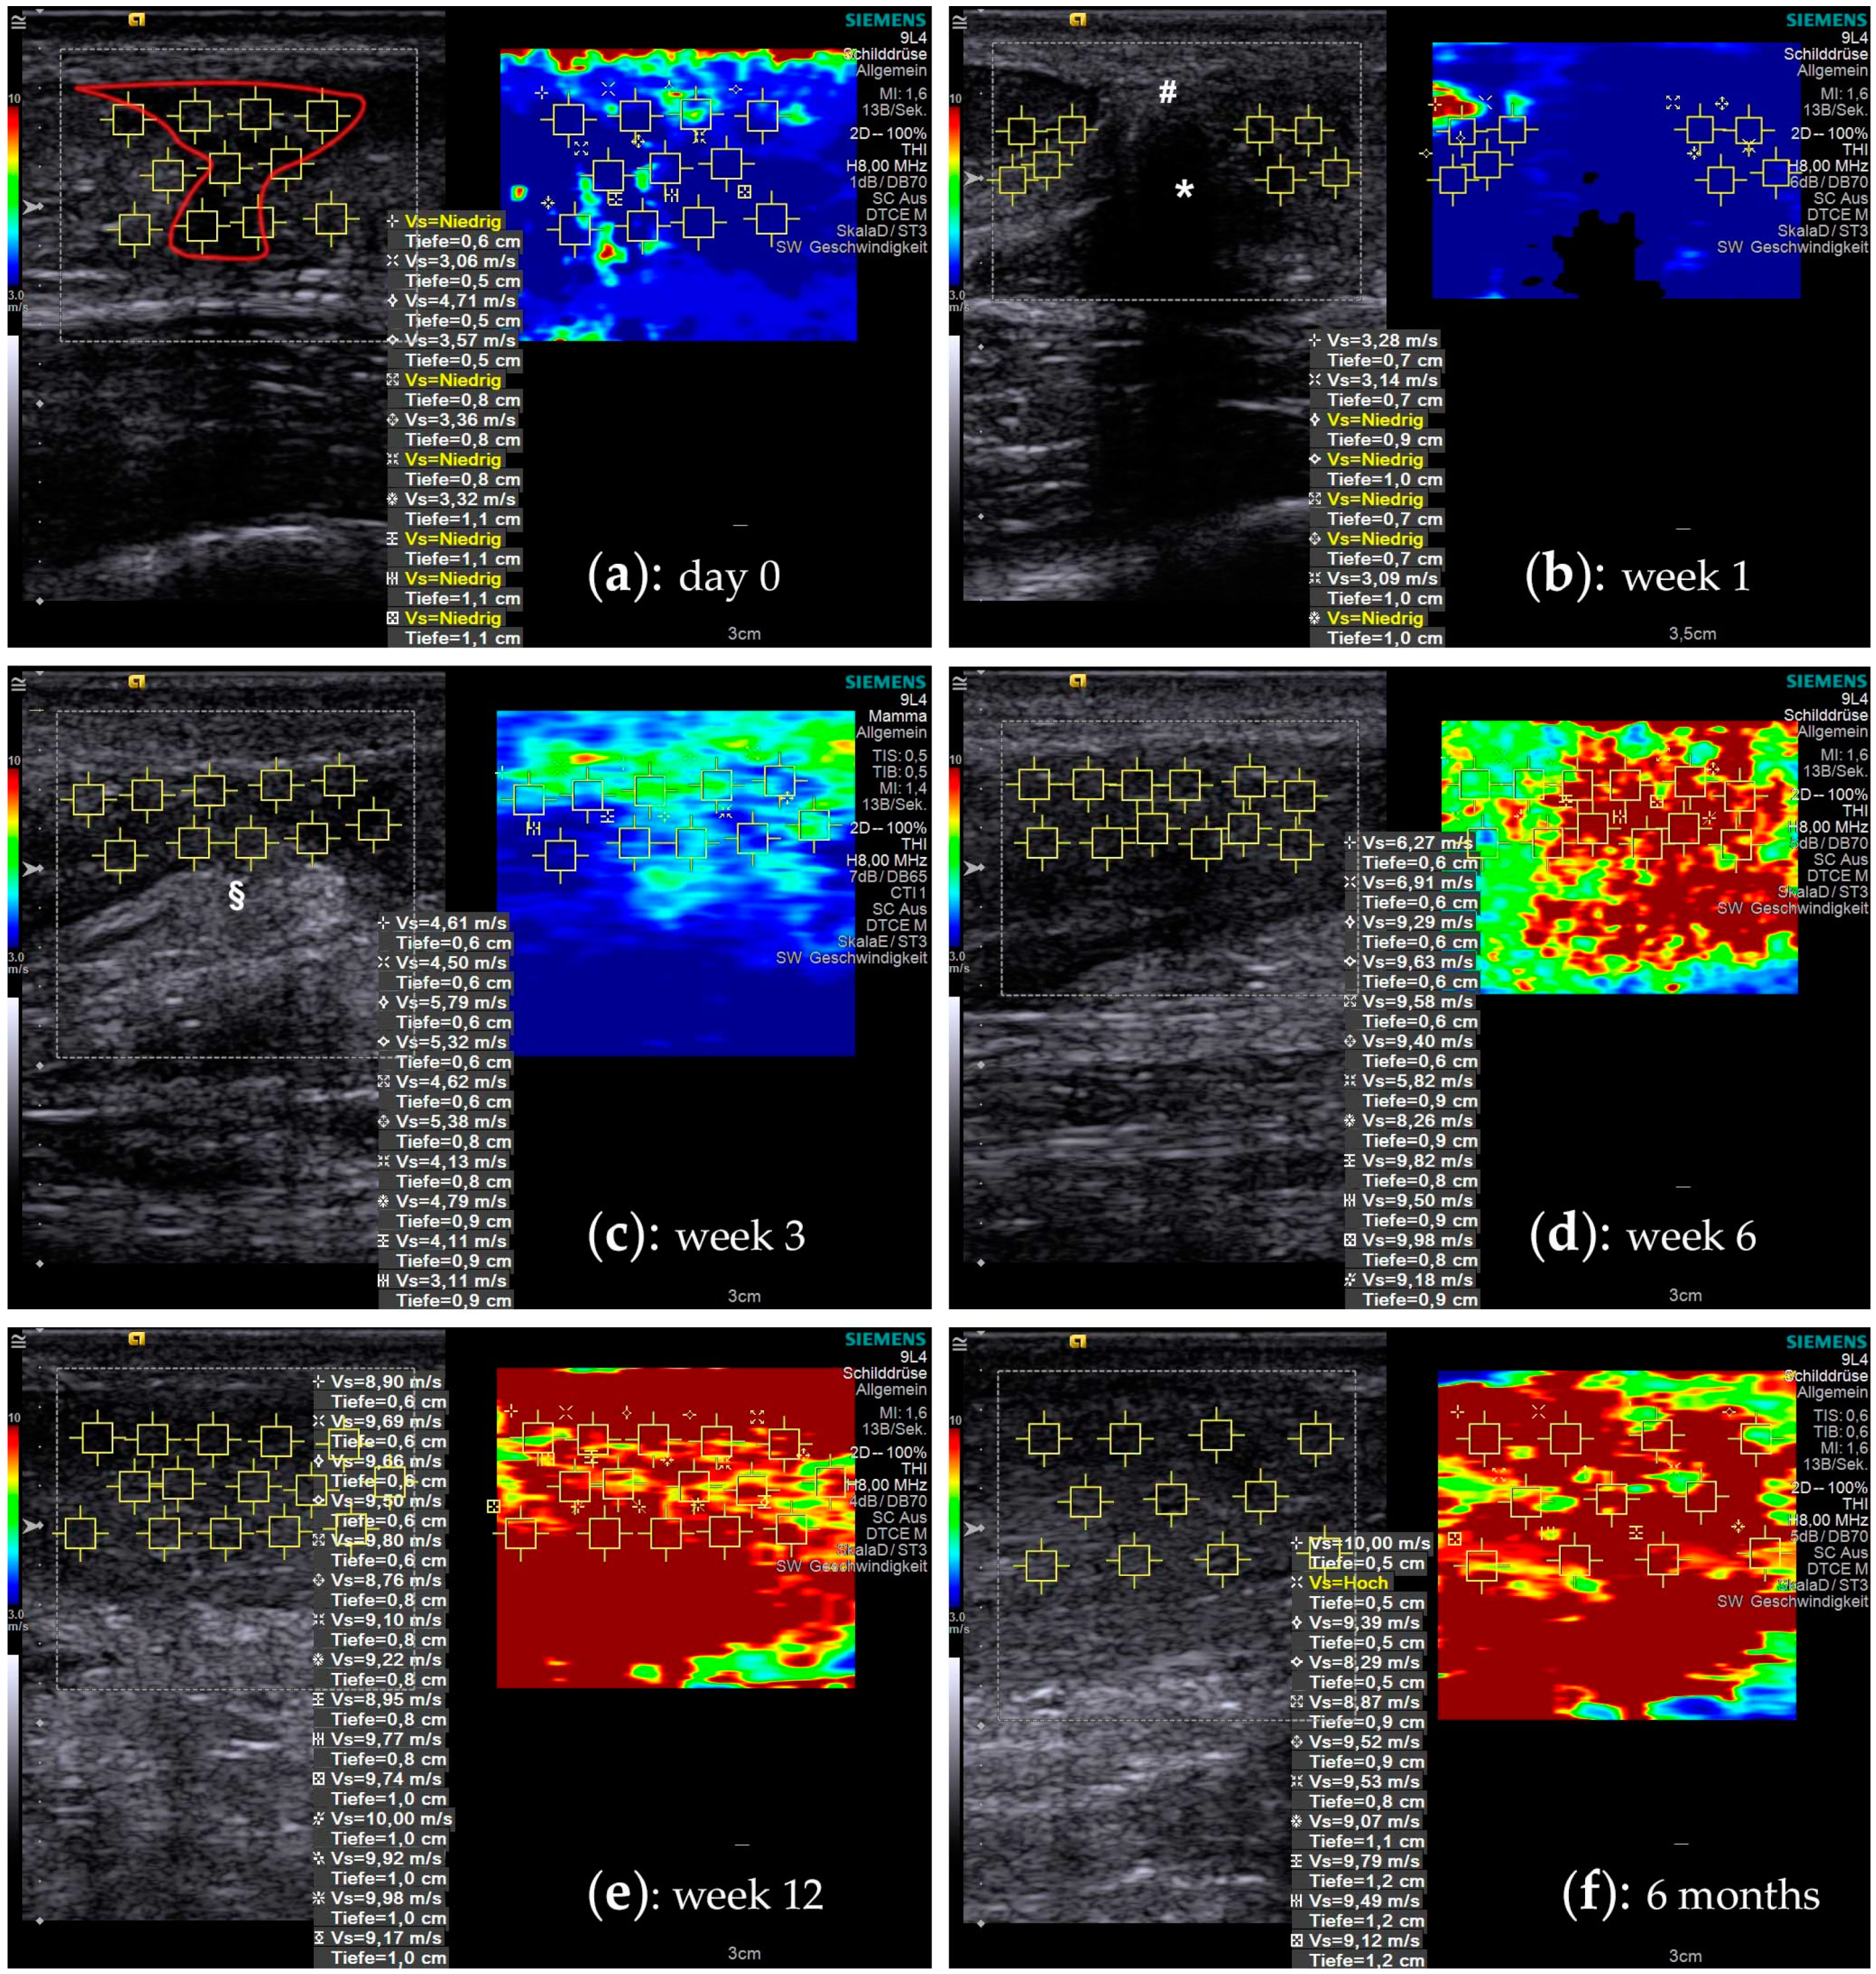

2.2. Shear Wave Elastography

2.3. Elastographic Behavior of Healing Tendons